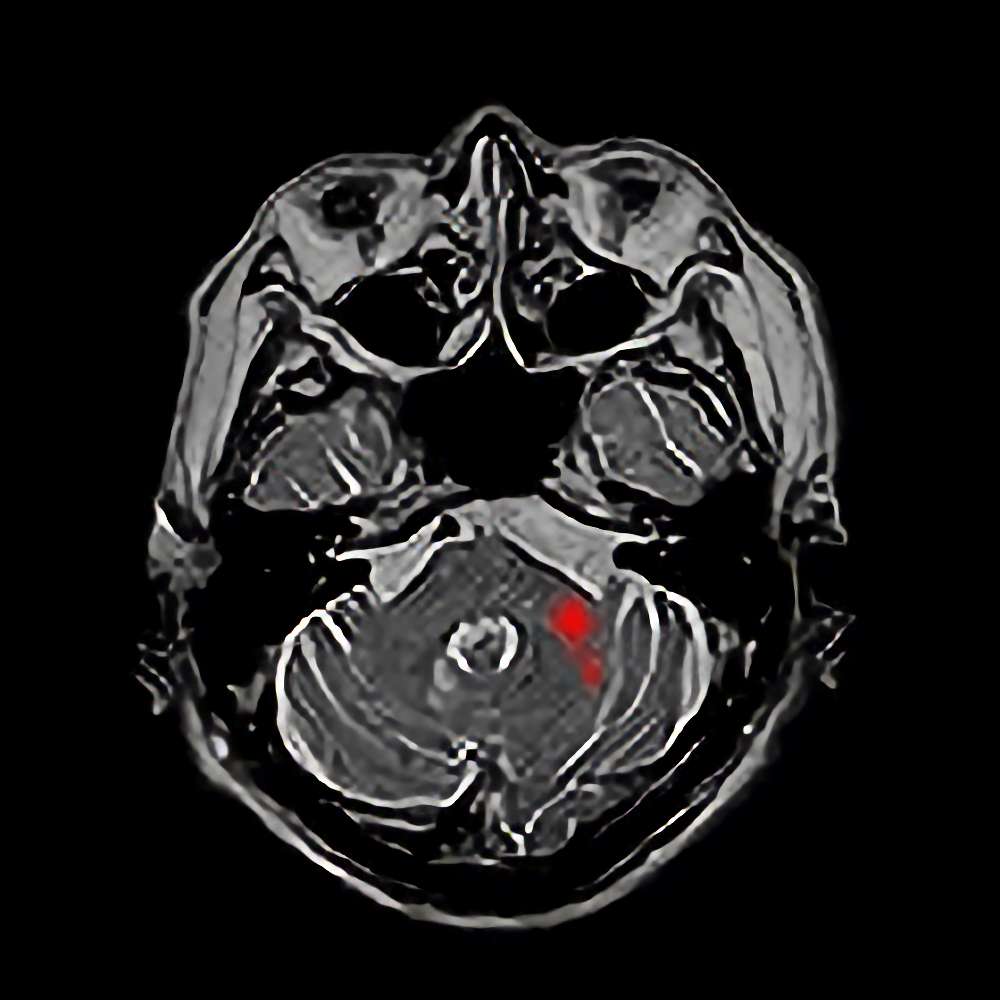

断層撮影

手術前1

手術前2